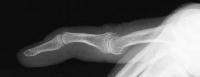

Clinical Example: Swan neck finger deformity

swan neck

recurvatum